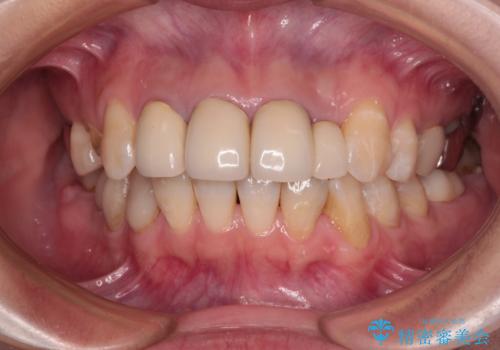

- 前歯のラミネートベニアの不自然な色合いを気にして来院された患者様です。

矯正治療後戻り防止のワイヤー周りにむし歯があったため、オールセラミッククラウンにて補綴することとしました。

ホワイトニングを併用し、治療前と比べて自然でとても明るい口元となりました。